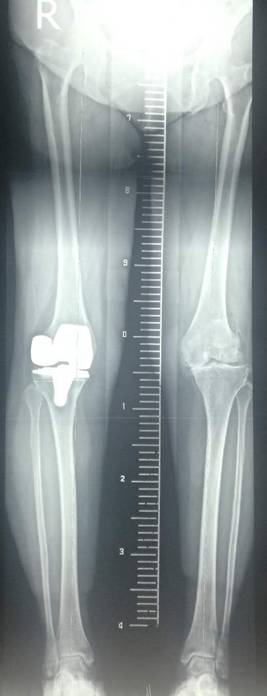

术前术后对比

全膝关节翻修术

全髋关节翻修术